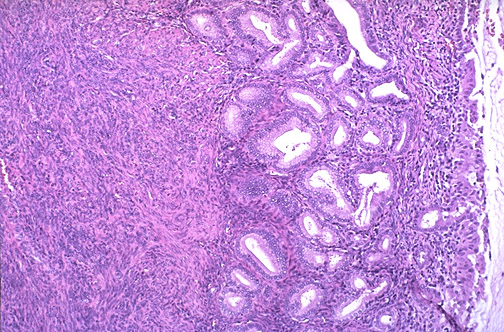

| At low power the uterus has a superficial columnar layer of cells, seen here overlying a stratum basalis layer with developing proliferative phase endometrium. The myometrium composed of smooth muscle bundles is below the endometrial layer which lines the central endometrial cavity of the uterus. |